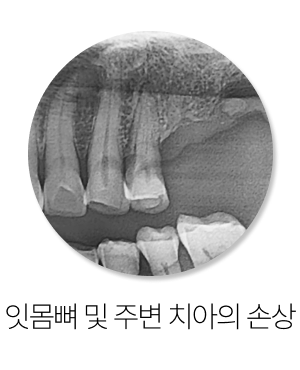

그래서 빠진 자리를 오래 비워두면 주변 치아들이 조금씩 움직이기 시작합니다.

뒤쪽 치아가 앞으로 기울어지거나, 맞물리던 반대편 치아가 아래로 혹은 위로 내려오는 정출 현상이 나타나기도 합니다.

이 변화는 아주 천천히 진행되기 때문에 스스로 알아차리기 어려운 경우가 많습니다.